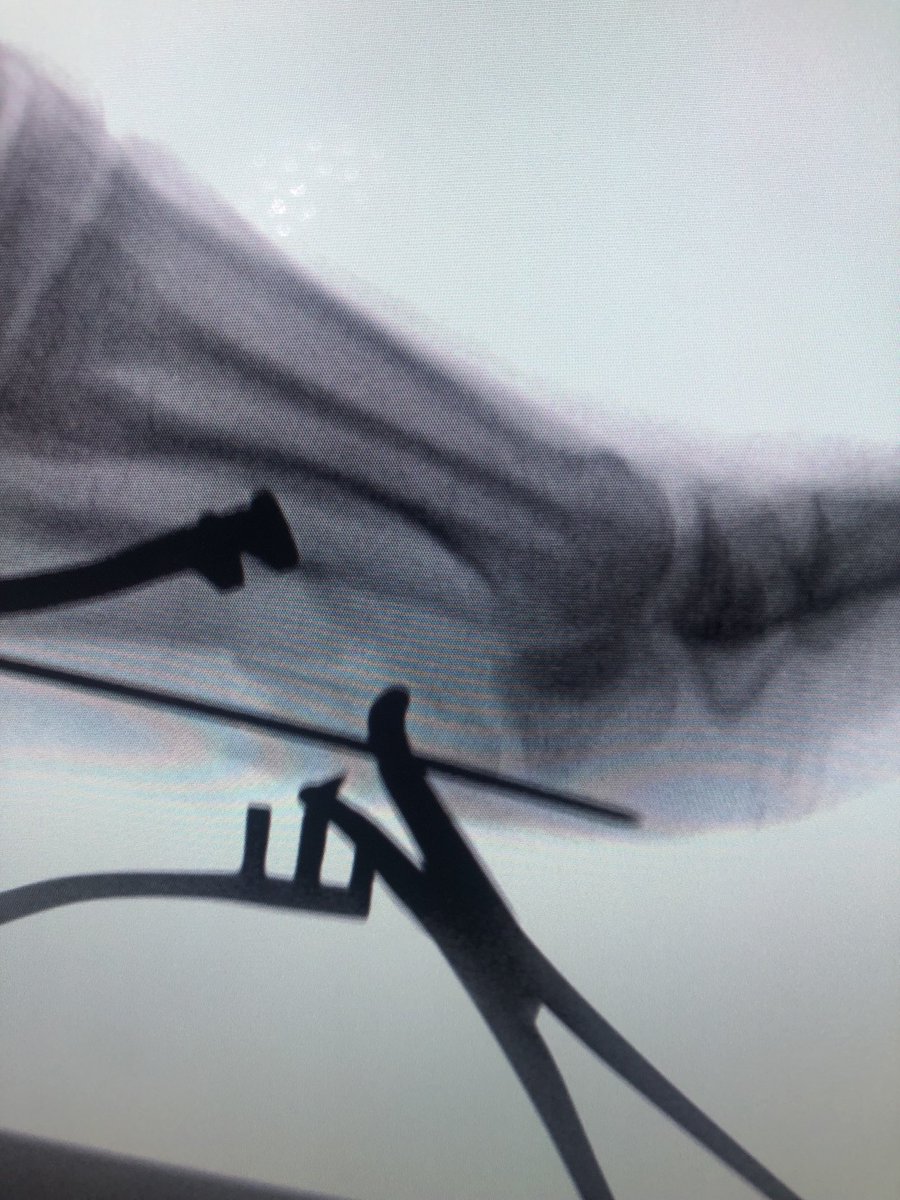

@Ric_Rag @traumaticum Yes. To help with initial reduction and flexion deformity

@dzbro_ @traumaticum Good job! Was the 1/3 tubular placed first to hold the reduction of the big GT fragment?

Say you work in an institution with a 'one implant fits all' strategy (Gamma3). How would you do adjuvent fixation for basicervicals or other weird neck/intertroch injuries? relatively seldom injury for me. Pulled this out of the hat but is there a better way? #orthotwitter